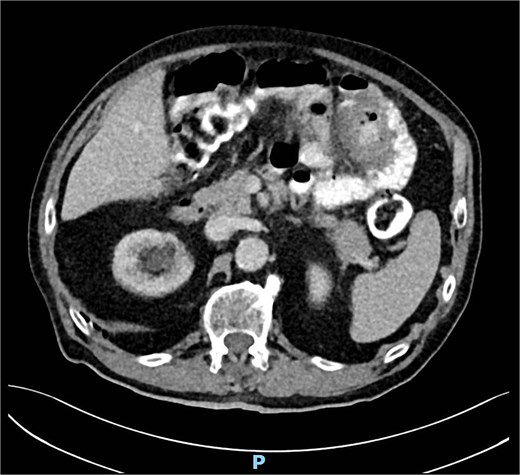

A computed tomography angiography (CTA) of the abdomen was performed, it showed a long segment of the small bowel with wall thickening in the right lower quadrant, accompanied by a inflammatory change in the mesenteric fat with multiple air bubbles, and free fluid in the pelvis, suggestive of hollow organ perforation (Fig. 1). Given the high suspicion of hollow organ perforation and clinical signs of peritonitis, an indication for exploratory laparotomy was established and performed as an emergency procedure. An antibiotic therapy with piperacillin/tazobactam was empirically initiated preoperatively.

CTA showing a long segment of small bowel with inflammatory wall thickening and fat stranding of the mesentery with multiple air bubbles.